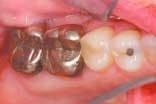

The upper and lower occlusal shots, as well as the four individual quadrants, are captured next. The four individual quadrant shots are the most powerful of the series. These are the shots where a patient can see old restorations, wear facets, recurrent decay, poor contour, etc. It is with the quadrant shot that the patient asks for dentistry. The doctor does not need to sell it!

Laboratory communication is perhaps the most important part of digital camera ownership. Traditionally, we have taken images of patients' teeth to communicate to our laboratory the shade and texture of the teeth for an indirect restoration. This is still a great application for digital cameras. The advantages of using a digital medium include the following:

Taking images of every indirect restoration will become routine. There is no reason not to take an image of every restoration. Laboratory technicians often are given only a set of stone models on which to build your restoration. When they have an image to go by, the quality of the restoration will be improved immeasurably. Patients will perceive that you are a high tech fastidious dentist who is going to give them a superior product.